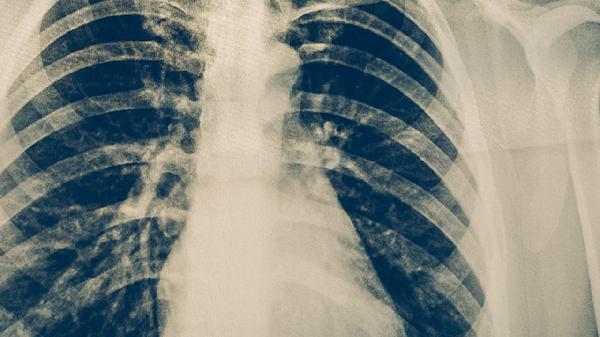

当胸平扫CT发现可疑病灶时,需通过增强CT观察血流特征,或进行经皮肺穿刺活检获取组织样本。支气管镜检查可直接观察气道内病变并取样,PET-CT能鉴别病灶代谢活性。肿瘤标志物如CEA、CYFRA21-1等辅助判断,但特异性不高。

建议长期吸烟者、有肺癌家族史的高危人群定期进行低剂量螺旋CT筛查。发现肺部异常阴影时,应遵医嘱完善相关检查,避免仅依赖单一影像学结果。日常需戒烟并减少油烟、粉尘接触,出现持续咳嗽、咯血等症状及时就诊。